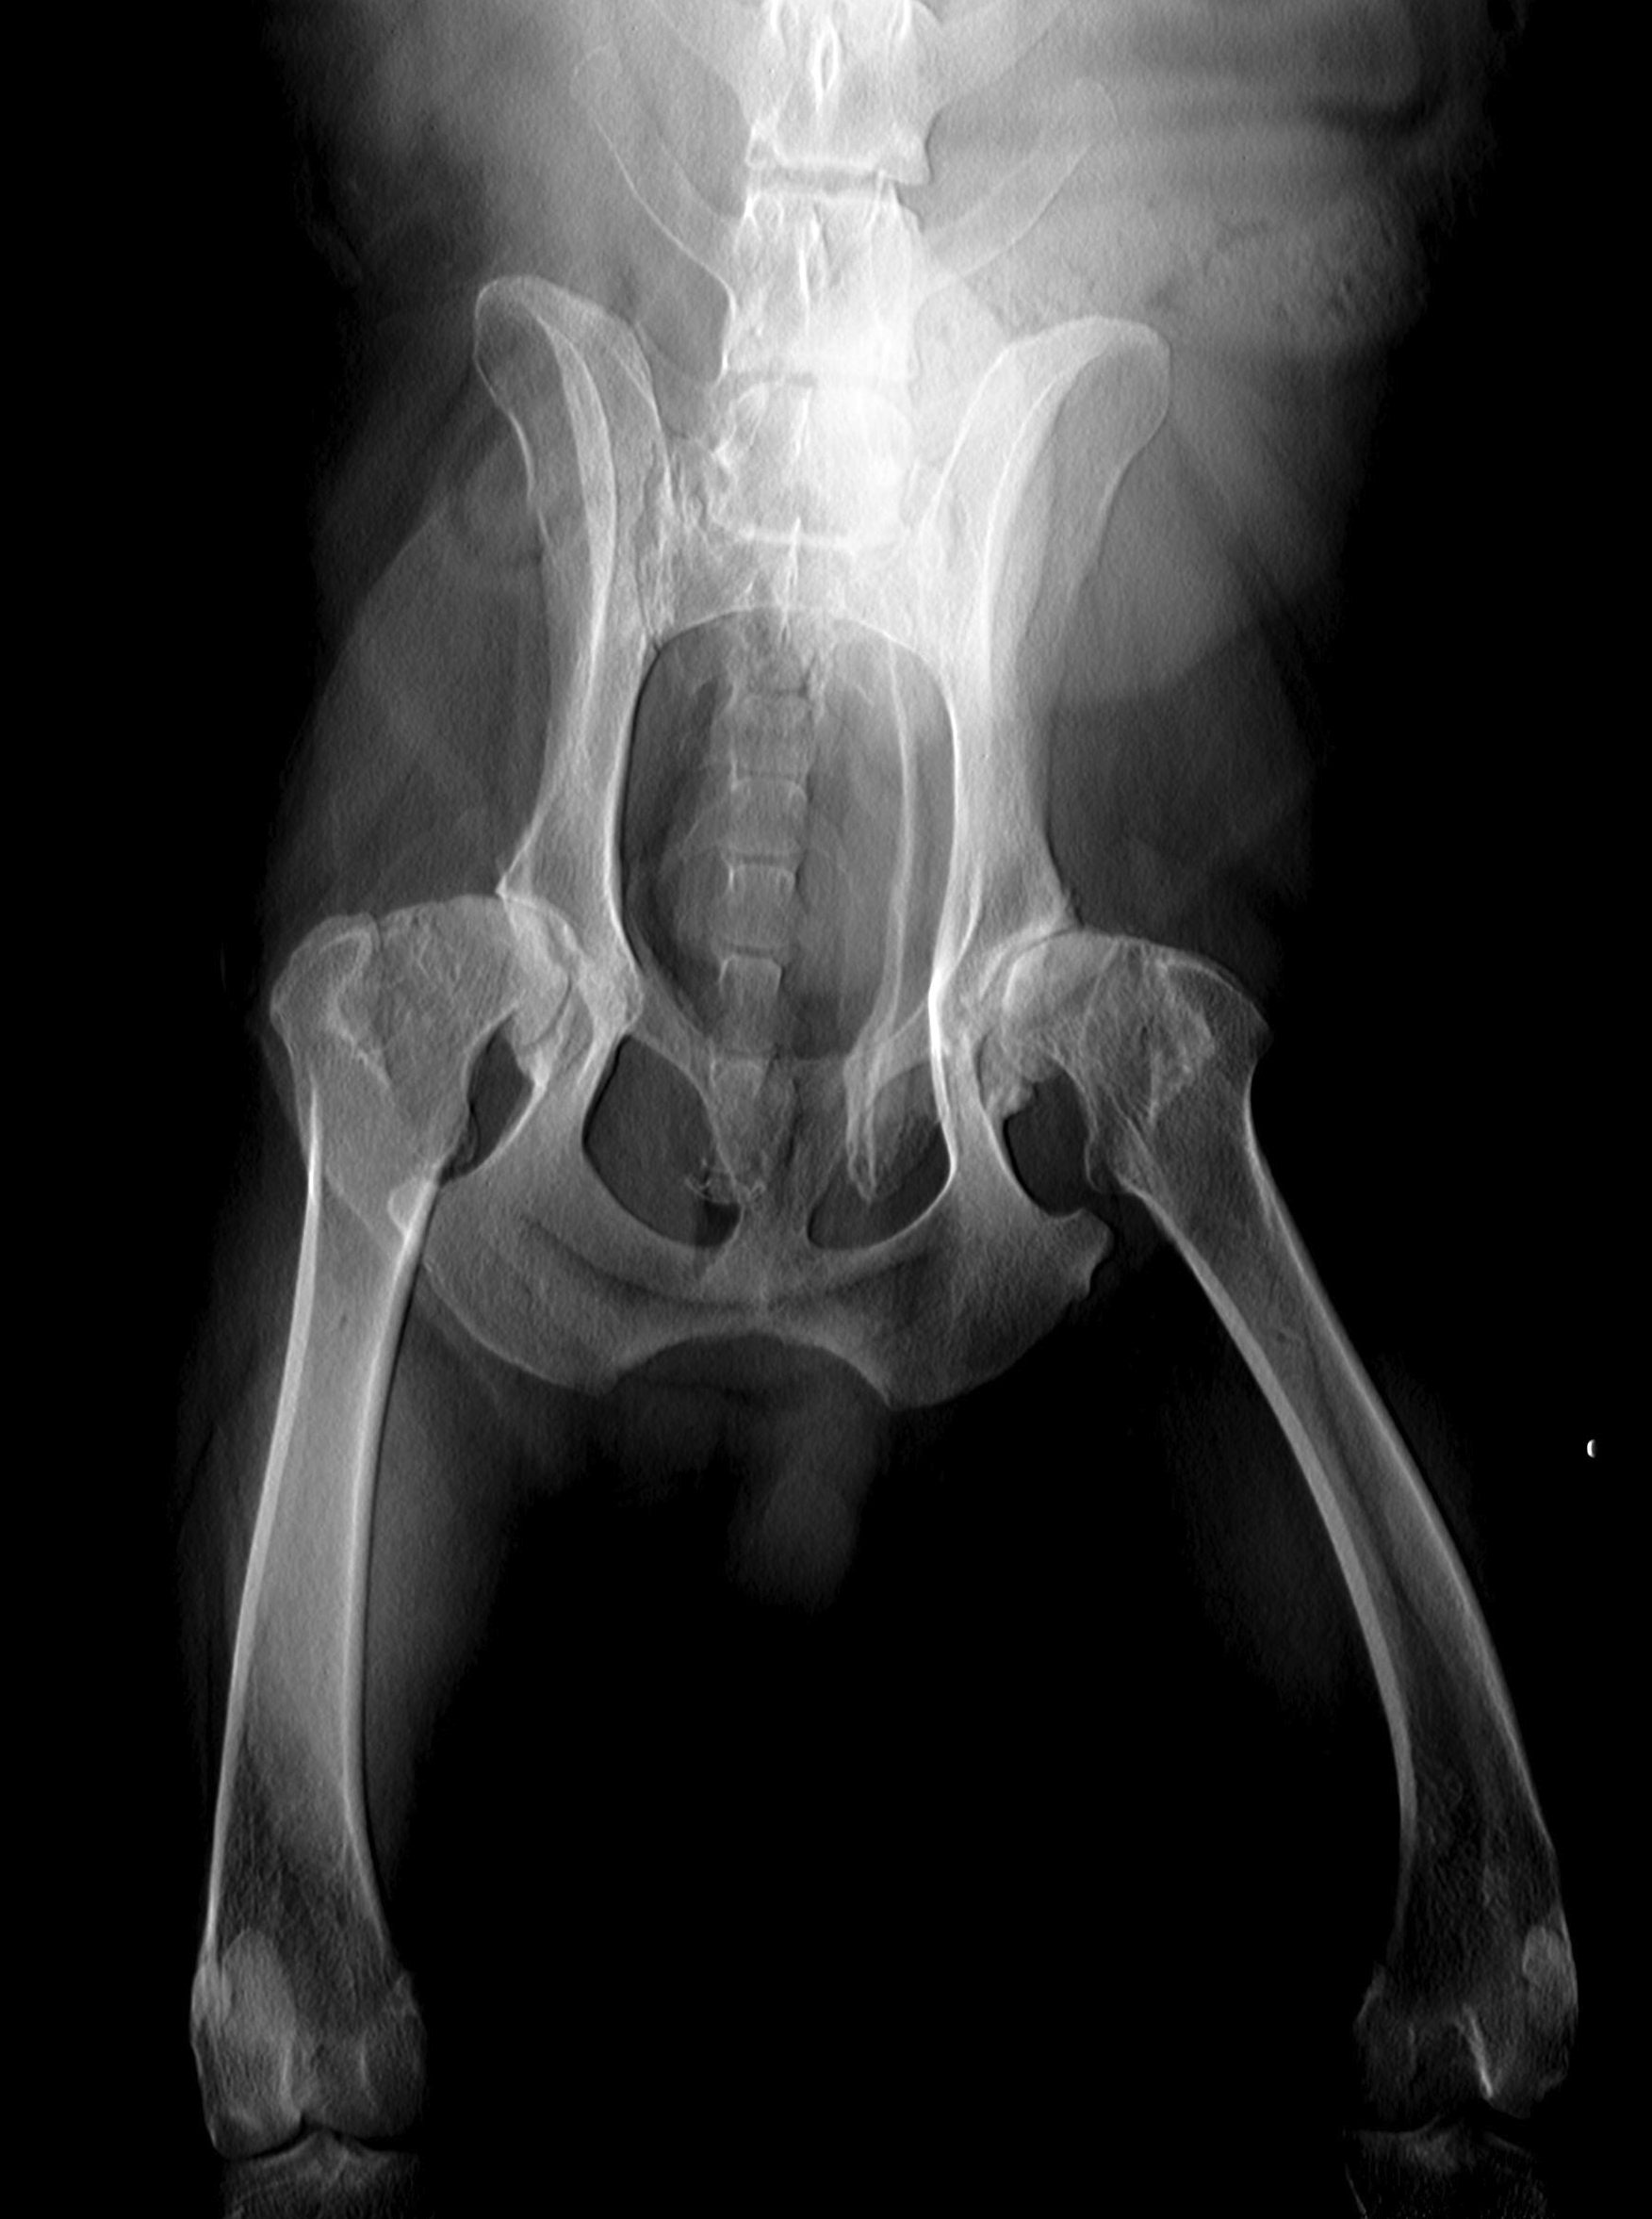

Radiographie des membres:

Pour la recherche de fractures mais également l’évaluation de différents problèmes articulaires comme l’arthrose ou la dysplasie.

Fracture du fémur et du bassin chez un chat

Évolution d’une dysplasie odo-fémorale en arthrose après quelques années